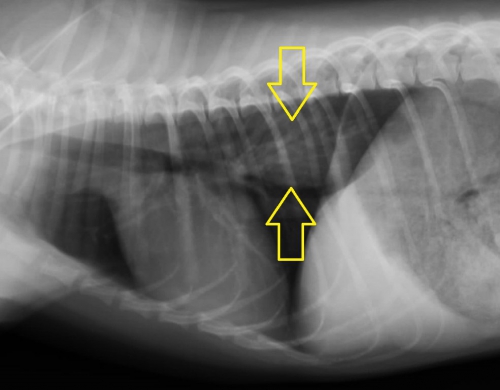

こういった場合、まず、レントゲン検査を行って異物の見当をつけます。下の胸部レントゲン写真で黄色い矢印に挟まれた部分が少し白っぽく見えるのがお分かりでしょうか?実は画像診断ではこういった特徴ですぐに胸部食道の異物を疑うことができます。

下写真は胸部レントゲン検査の画像です。【ケース1】と同様に黄色の矢印の間にわずかに白いエリアが見られます。

下の写真が胸部レントゲン写真です。黄色い矢印に挟まれた「白く細長い異物が見えると思います。この場所は胸部食道の心基底部(心臓の上)に近い部分で、食道閉塞を起こしやすい場所です。写真ではまた。食道閉塞に伴って飲み込んだ空気によって食道拡張がみられています。(右の赤い矢印の間)